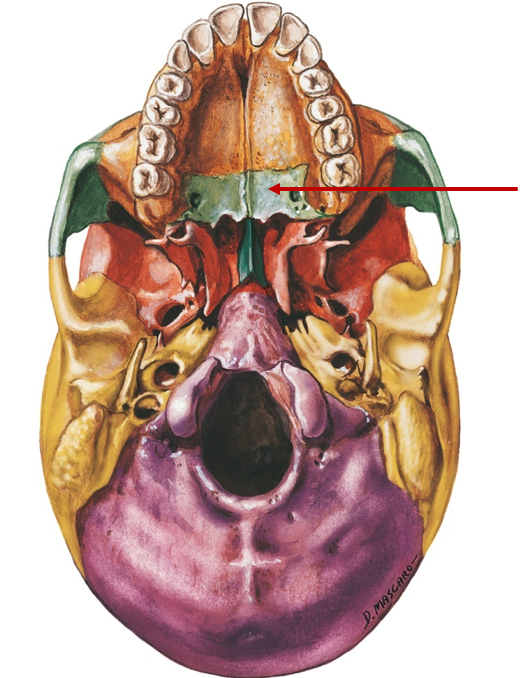

Palatine

Tiny, back of roof of mouth

Vomer

Posterior portion of septum

Foramen magnum

Big hole, spinal cord runs through

Occipital condyle

Knobs, head movement

Jugular foramen (with temporal bone)

Hole for blood vessels, in temporal and occipital